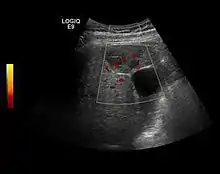

Hemangioma

It is the most common liver tumor with a prevalence of 0.4 – 7.4%. It is generally asymptomatic but also can be associated with pain complaints or cytopenia and/or anemia when it is very bulky. It is unique or paucilocular. It can be associated with other types of benign liver tumors. Characteristic 2D ultrasound appearance is that of a very well defined lesion, with sizes of 2–3 cm or less, showing increased echogenity and, when located in contact with the diaphragm, a "mirror image" phenomenon can be seen. When palpating the liver with the transducer the hemangioma is compressible sending reverberations backwards. Doppler exploration reveals no circulatory signal due to very slow flow speed. CEUS investigation has real diagnosis value due to the typical behavior of progressive CA enhancement of the tumor from the periphery towards the center. The enhancement is slow, during several minutes, depending on the size of hemangioma and on the presence (or absence) of internal thrombosis. During late (sinusoidal) phase, if totally "filled" with CA, hemangioma appears isoechoic to the liver. Deviations from the above described behavior can occur in arterialized hemangiomas or those containing arterio-venous shunts. In these cases, differentiation from a malignant tumor is difficult and requires other imaging procedures, follow up and measurements of the tumor at short time intervals.[4]